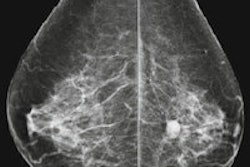

Digital mammography can be performed with either computed radiography (CR) or digital radiography (DR) technology, and which is used can affect radiation dose and performance characteristics, which are important issues affecting the program's quality, according to doctoral student Lore Timmermans, from the department of basic medical sciences at Ghent University in Belgium, and colleagues.

Most significantly, the researchers found that CR and DR affected radiation dose in different ways. When compared with analog mammography, mean glandular dose (MGD) for CR increases 30%, while a decrease of 30% in dose was found for DR.

In terms of the mean glandular dose, several studies have reported dose increases when film-screen mammography is replaced by CR technology, as is the case in this study.